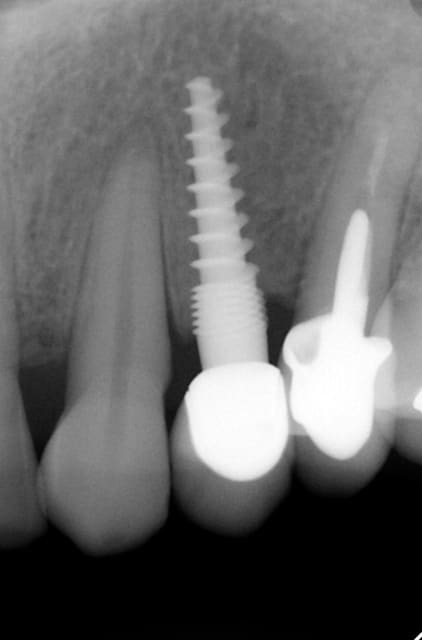

Oui ca semble ....sur la opg radio tu peux voir la situation seulement deux semaines après l´implantation immédiate 34 jusqu´à 36 et 45, les derniers 2 photos montrent la même situation après un an ( où on a enlevé la supra construction pour un contrôle). Sur ce cas je voulais montrer la bonne régénération osseuse et de la gencive.

Oui,c´est un Prep cap zircone , que je cémente juste après l´implantation immédiate pour mieux former la gencive. Les implants monoblocs ont étés implantés entre 40 et 60 Ncm . Les photos 6 et 8 on voit les prep cap juste après l´implantation immédiate ce sont des sortes de "couronnes" pré fabriquées.

Oui , tu as raison pour la 45, en fait quand j´ai enlevé la 45 j´ai choisi l´axe comme ca ( dans l´os dur et en bon santé) parce que c´etait ici que je pouvais avoir la stabilité ( pour cet implant à 50 Ncm.

Voilà une patiente que je revois à deux ans apres la pose d'un monobloc Classic line 3,5/12mm et prep cap zircone 12 degres 2/2 en 24.

Radios 1,2,3 photo 1= jour de la pose de l'implant.

radio 4 photo 2 et 3= 8 semaines post pose de l'implant, ceramiques scéllées.

Radio 6, photo 4 et 5 controle à 24 mois.

Deux ans plus tard, la gencive a recouvert la zircone et on observe à la radio un gain osseux au niveau des micros spires.